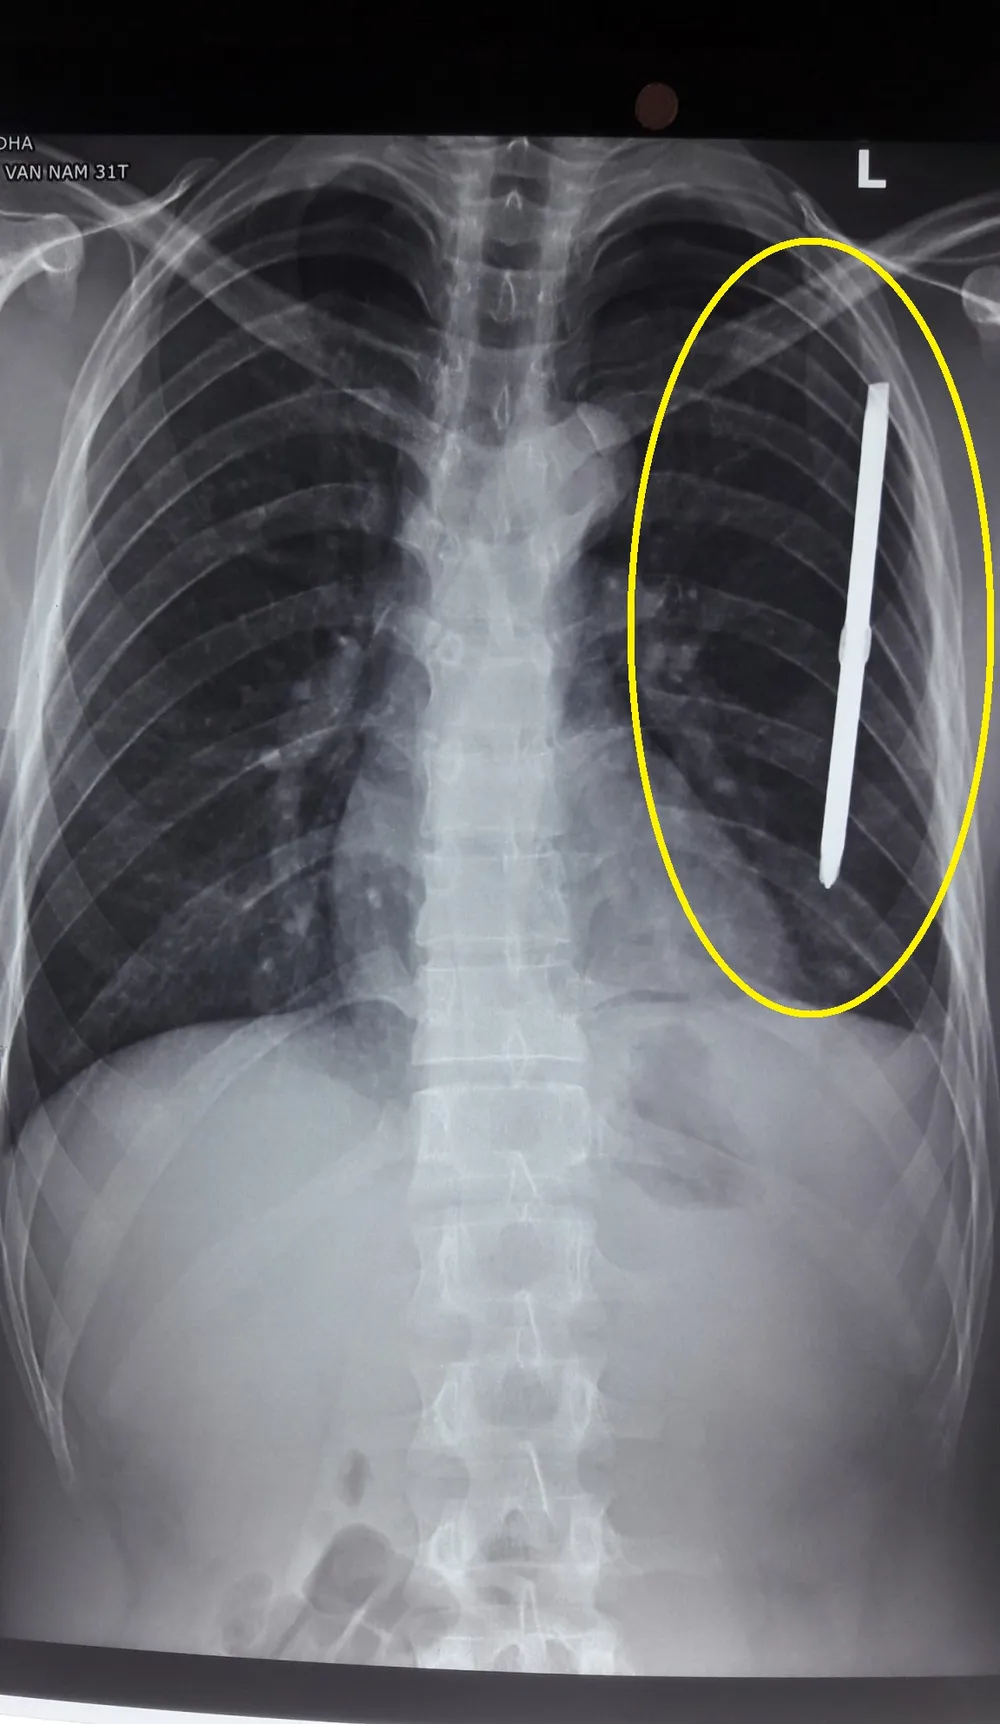

Hình ảnh dị vật qua phim chụp X.Quang

Tại đây, qua tiến hành chỉ định chụp X Quang, các bác sĩ phát hiện có một dị vật dài gần 20cm đâm xuyên vào thành ngực trái bệnh nhân N.V.N.

Tại đây, sau khi làm các xét nghiệm cần thiết, chụp X Quang và chuyển bệnh nhân để phẫu thuật cấp cứu, các bác sĩ đã tiến hành lấy ra ngoài dị vật là 1 chiếc tuốc nơ vít dài gần 20cm, rất gần tim.